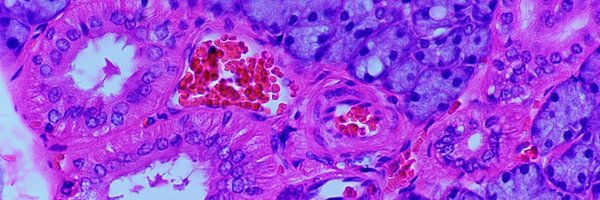

A special seminar from @JarodForer visiting from @uoregon to tell us about his PhD so far, specifically a project characterizing the fluid response to injury in rat Achilles tendons. Thanks for stopping by the institute to share your work!

How is a tendon like a colander? @JarodForer crushed his 3 min thesis presentation as he explained how fluid micro circulation can be a target for new therapeutic approaches for tendon injuries. @UOKnightCampus @WuTsaiAlliance #ORS2024

Jarod Forer presented his poster (1313) “Microcirculation of the Rat Achilles Tendon Is Dependent on Particle Size." He is also presenting as a 3 Minute Thesis Finalist in the 2:15 pm session in room 203 today at #ORS2024